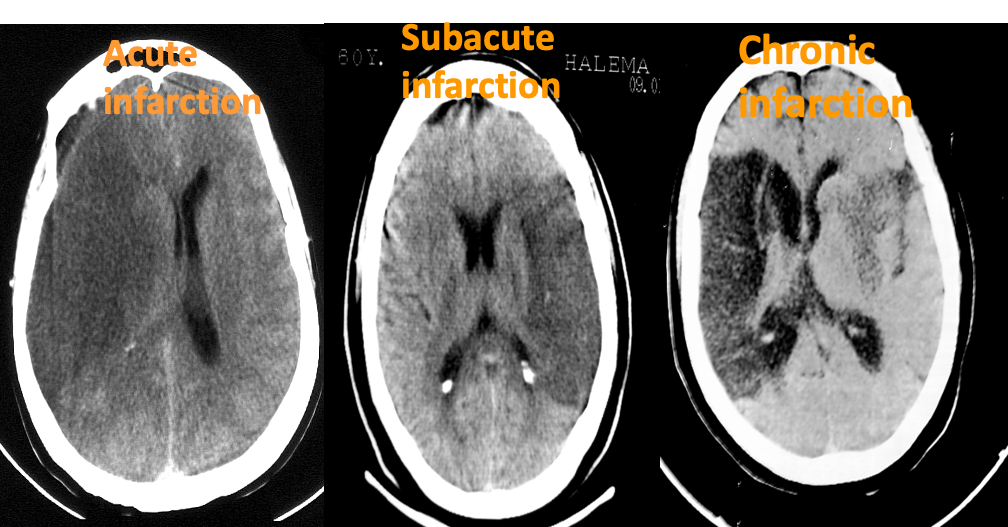

Is a hypodense lesion

- Can be acute , Subacute or chronic

- Has a vascular territory

Has a cortical distribution

Types of infacrtion

A) Acute Infarction; Hypodense lesion + edema ---β mass effect - contralateral pressure

B) Subacute Infarction; hypodense lesion, no edema -β No mass effect

C) Chronic Infarction; Hypodense lesion, no edema.loss of volume (gliosis)

β negative mass effect on the ventricle and sulci (Evaccu dilatation) - ipsilateral midline shifting